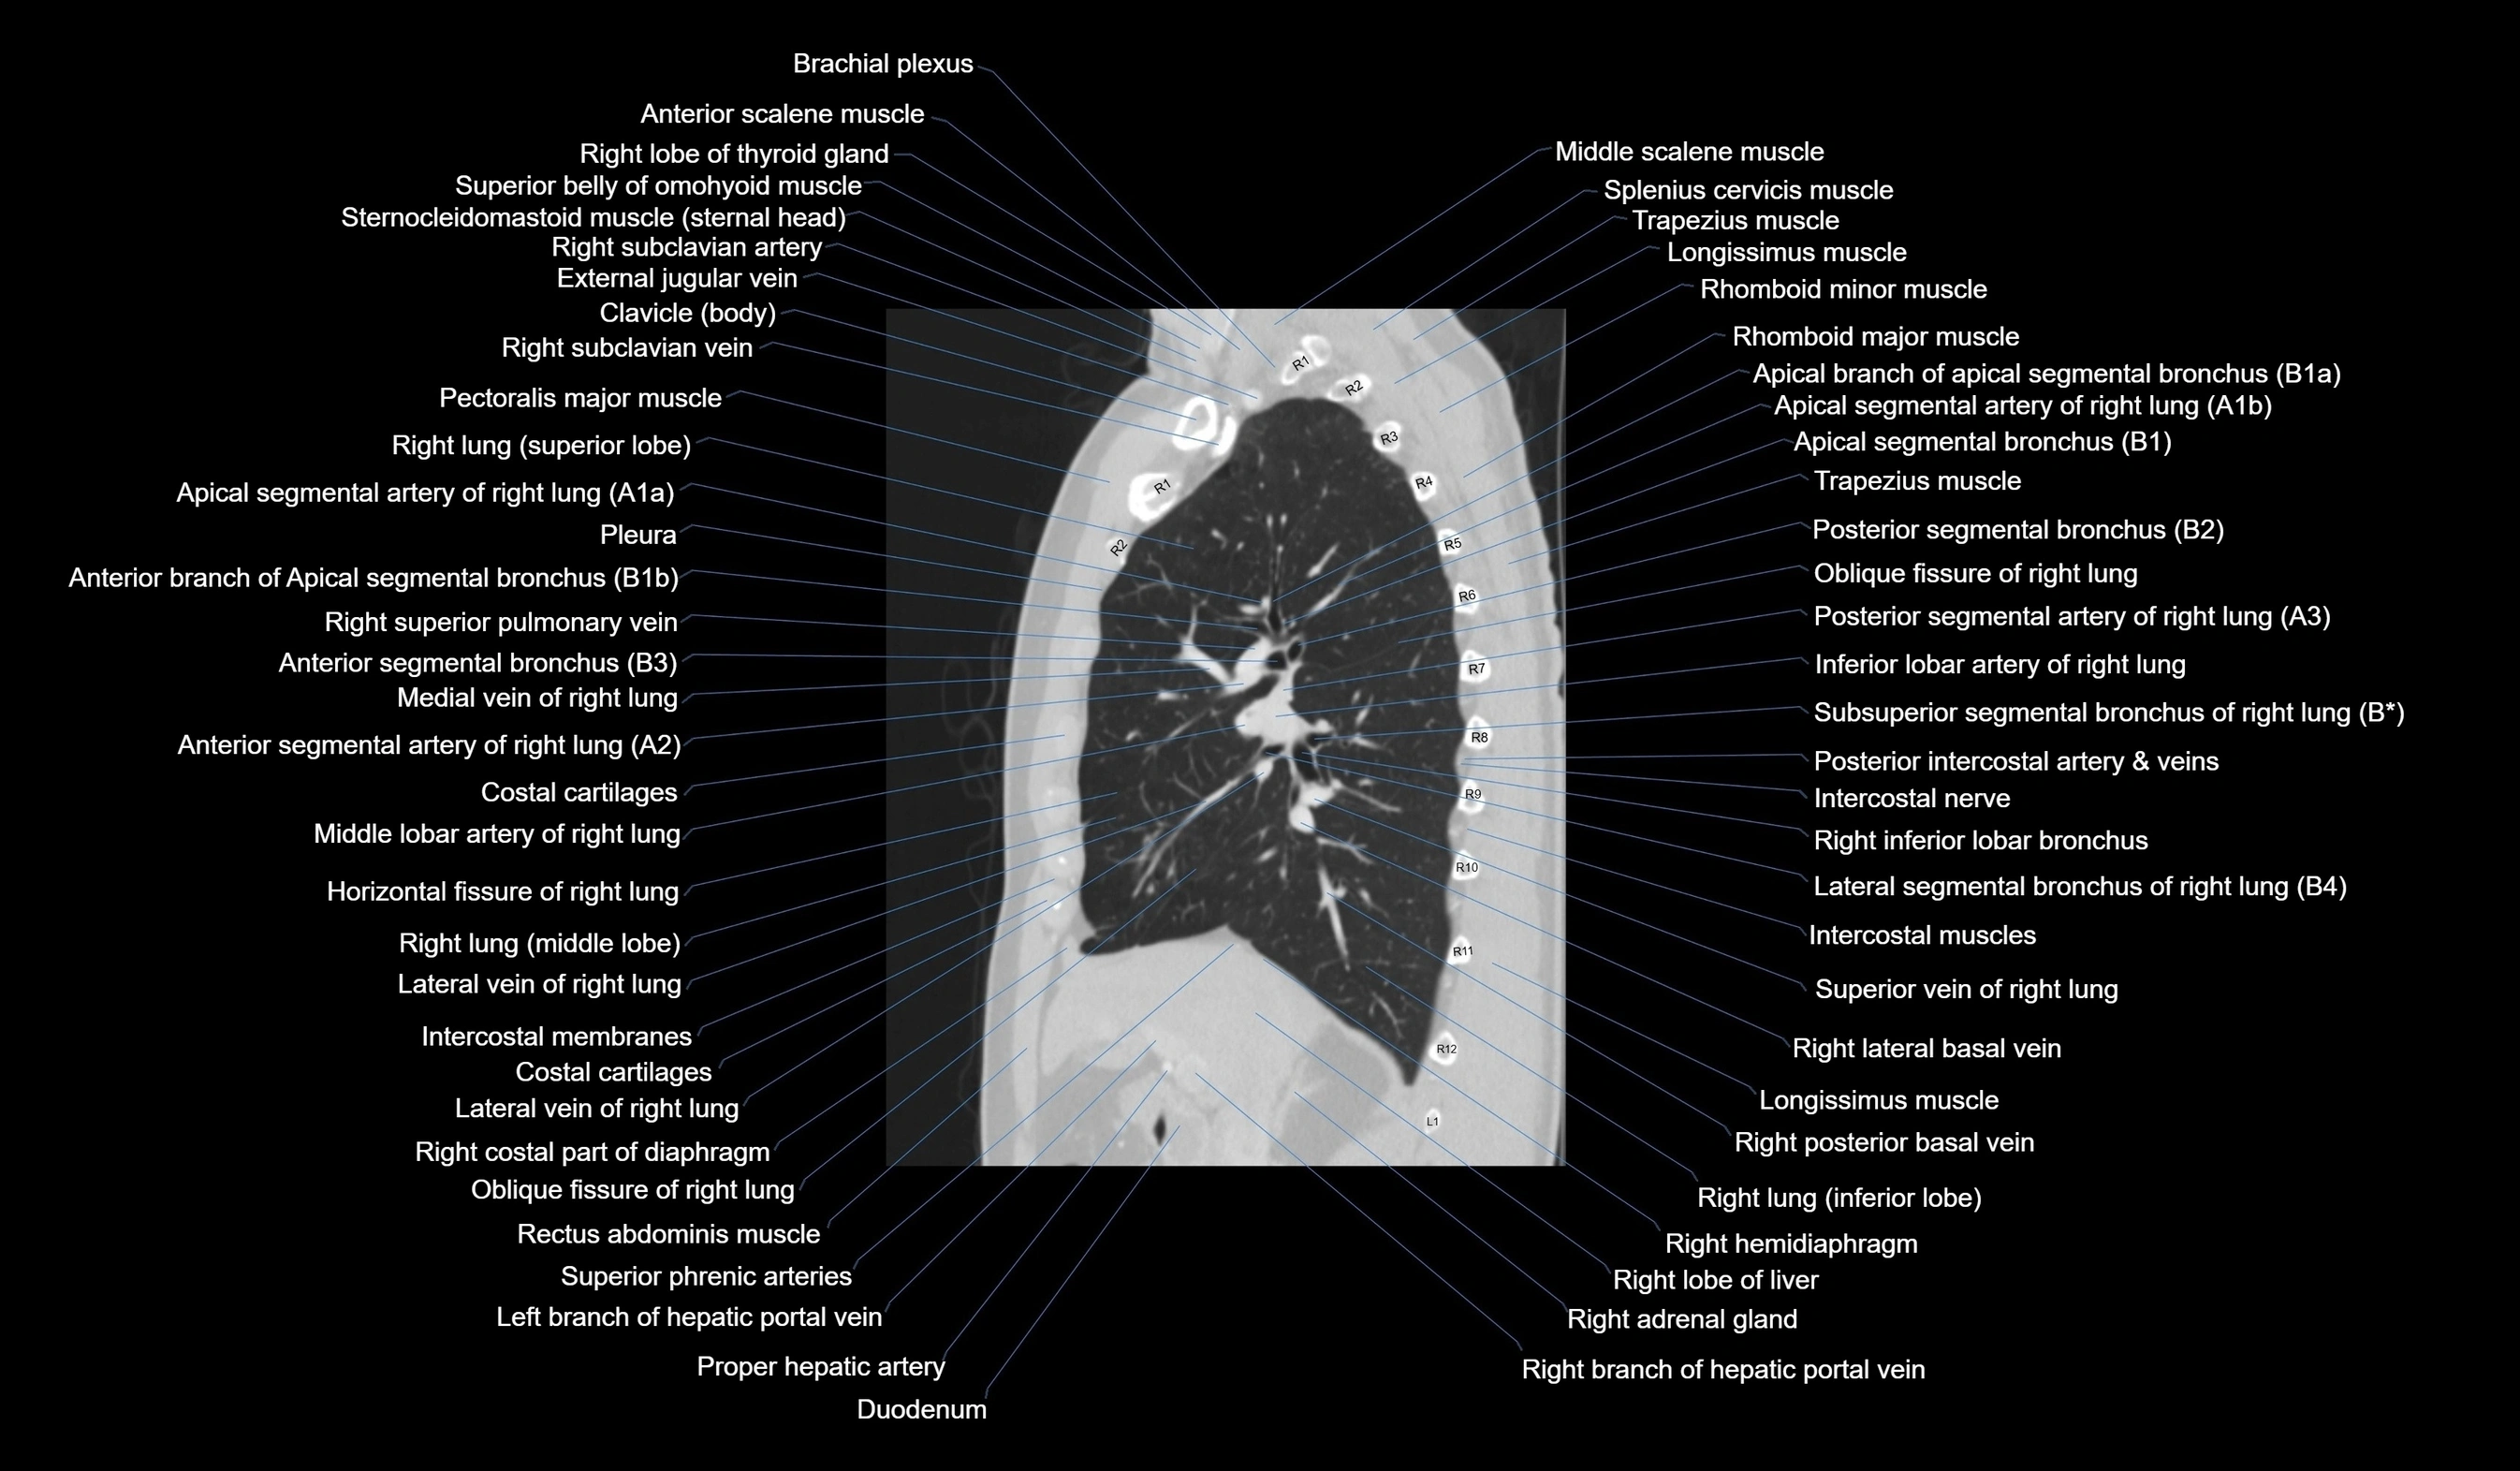

- Right lung (superior lobe)

- Right lung (inferior lobe)

- Right lung (middle lobe)

- Horizontal fissure of right lung

- Oblique fissure of right lung

- Apical segmental bronchus of right lung

- Posterior segmental bronchus of right lung

- Anterior segmental bronchus of right lung

- Superior segmental bronchus of right lung (B6)

- Lateral basal segmental bronchus of right lung (B9)

- Lateral segmental bronchus of right lung

- Superior vein of right lung

- Inferior lobar artery of right lung

- Middle lobar artery of right lung

- Lateral vein of right lung

- Medial vein of right lung

- Subsuperior segmental artery of right lung

- Superior segmental artery of right lung

- Posterior segmental artery right lung